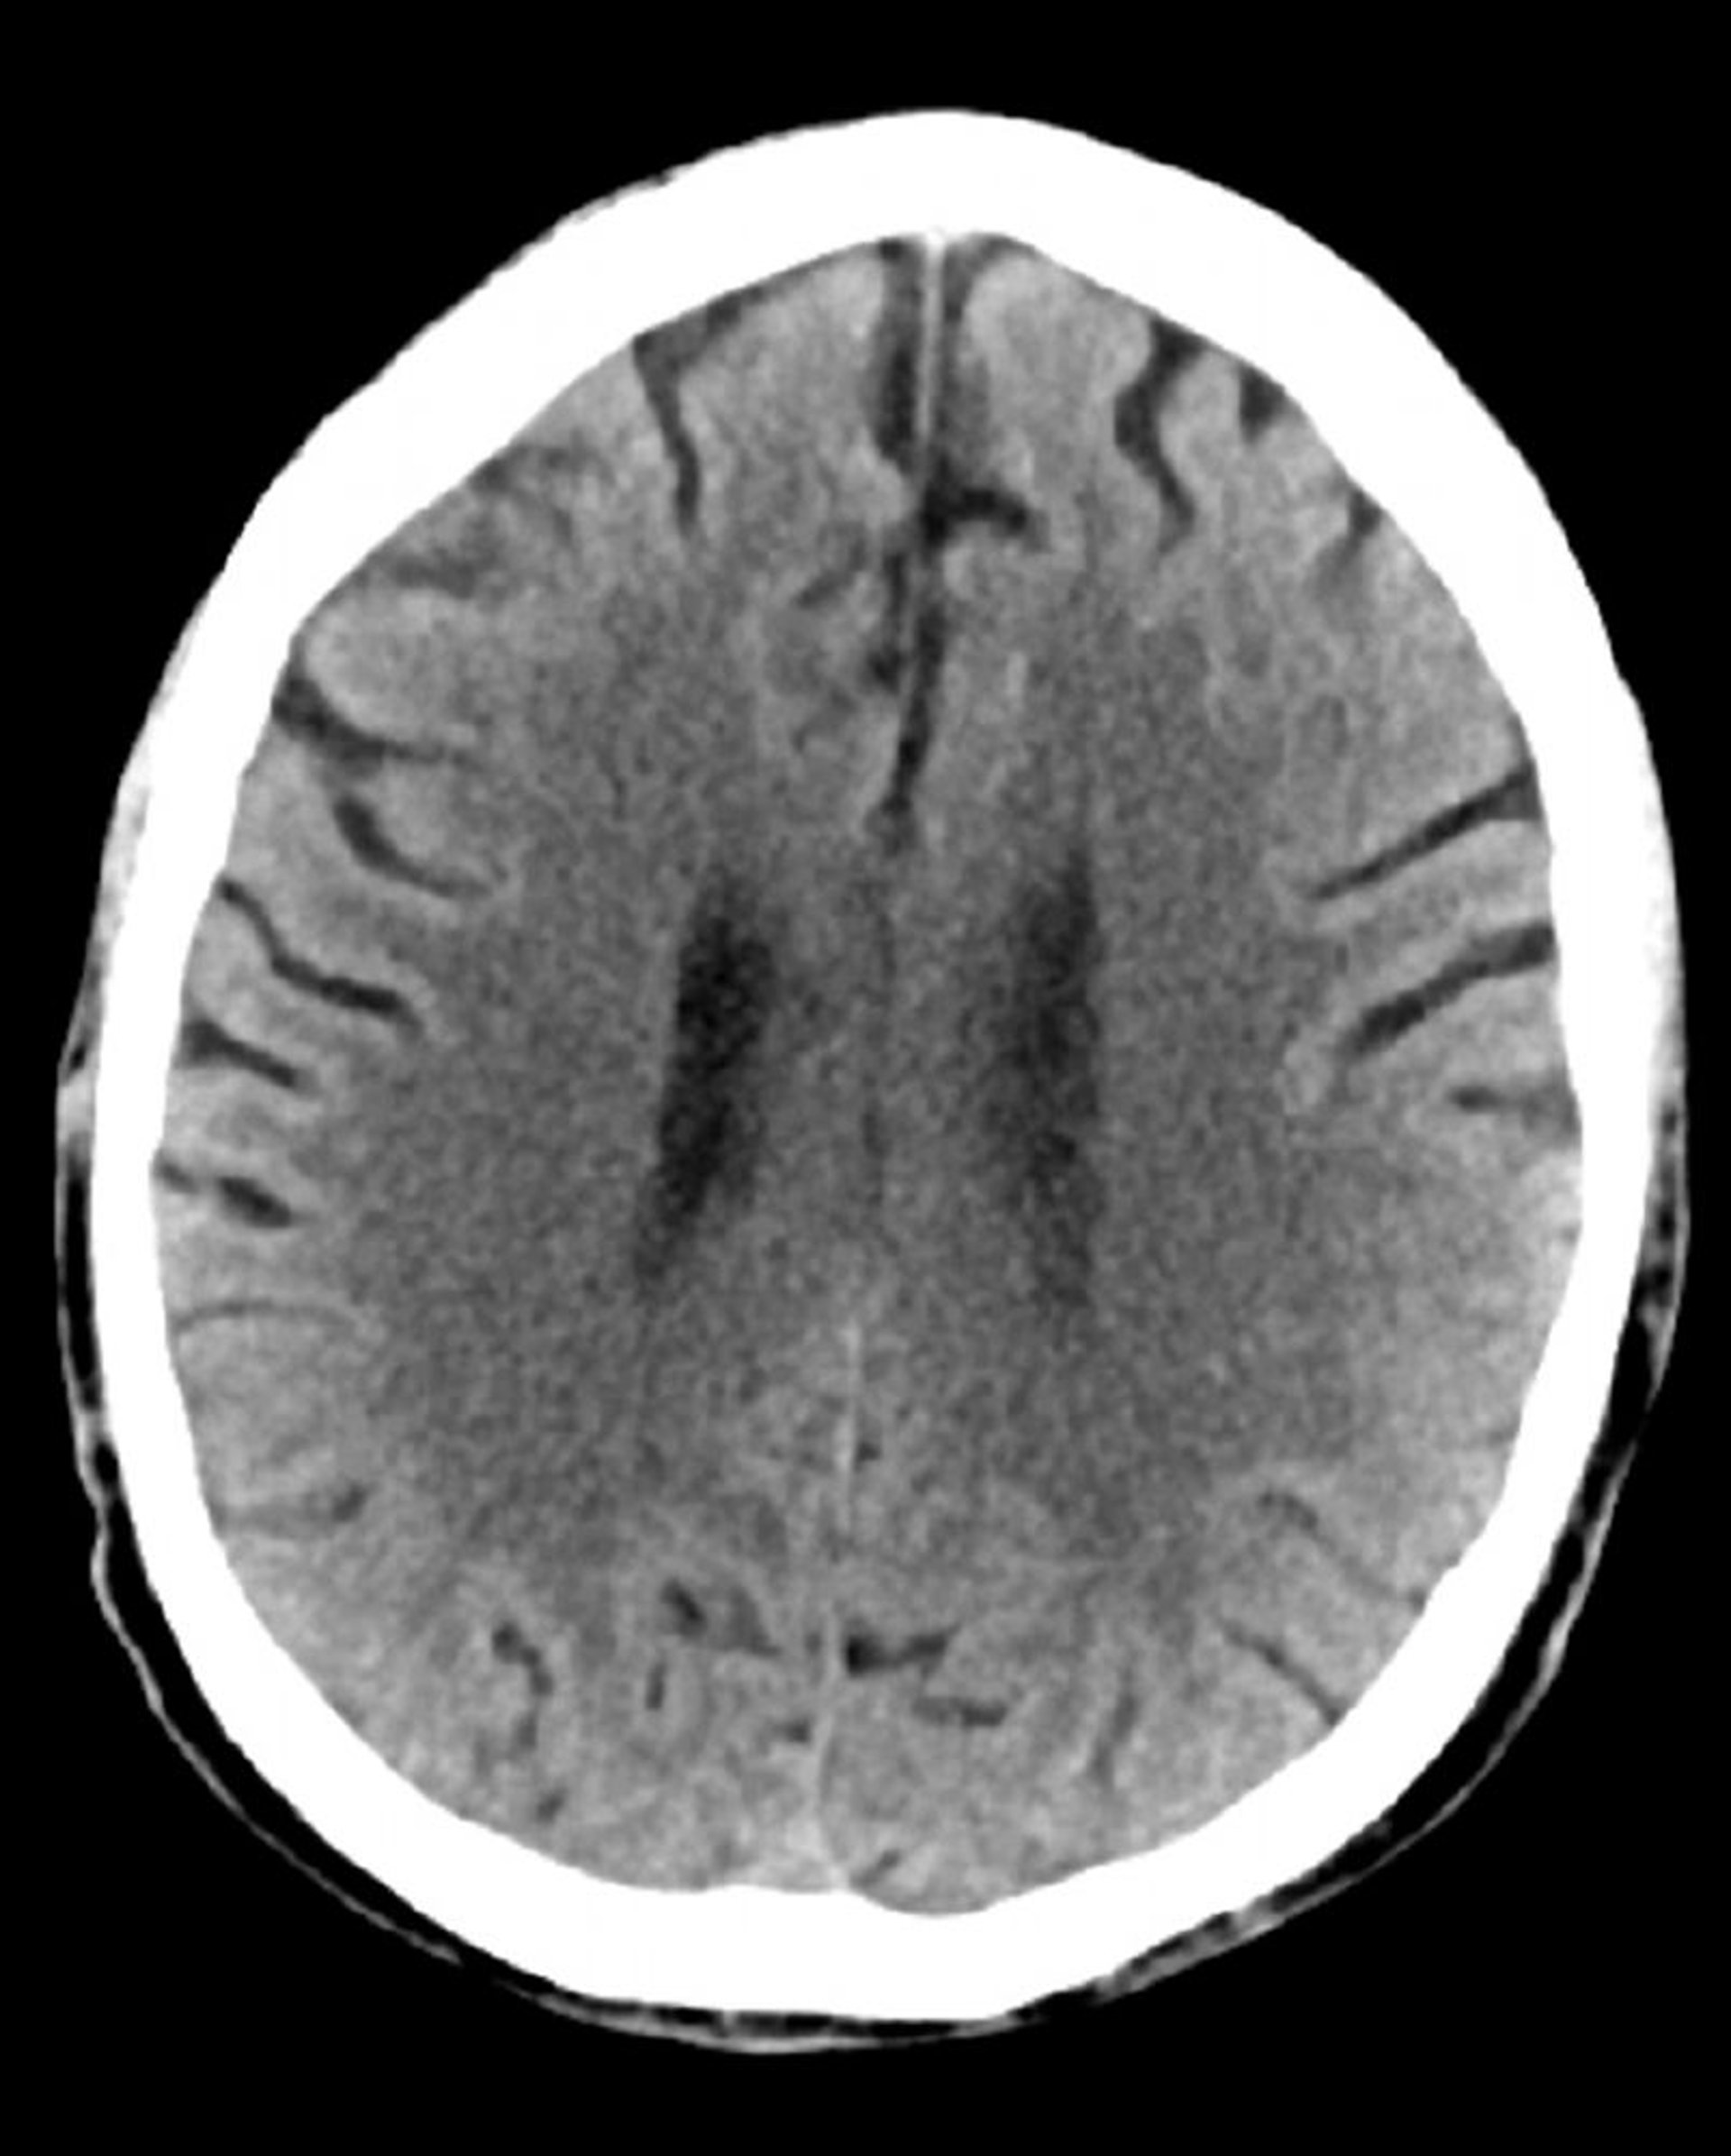

Normal Head CT Scan (Adult, Age 74) – Slide 3

This image is a normal CT scan of the head of an adult aged 74. When compared with the normal CT scan of the head of a 30-year-old, the ventricles and sulci are larger. These findings are normal in this age group.